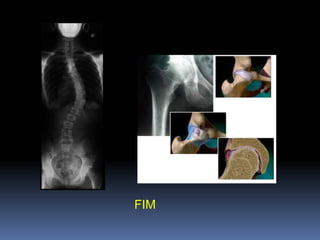

DiagnósticoHistória clínicaExame físicoAvaliação laboratorialQuadro radiográficoRX

Densitometria óssea (padrão-ouro)Índice de Singh

Quadros Radiológicos